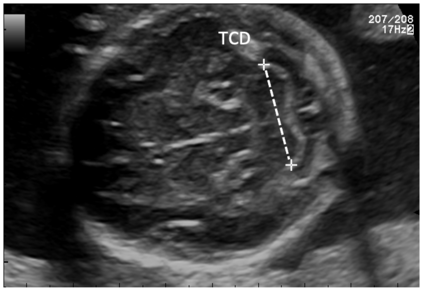

Deep-learning (DL) algorithms are becoming the standard for processing ultrasound (US) fetal images. Despite a large number of survey papers already present in this field, most of them are focusing on a broader area of medical-image analysis or not covering all fetal US DL applications. This paper surveys the most recent work in the field, with a total of 145 research papers published after 2017. Each paper is analyzed and commented on from both the methodology and application perspective. We categorized the papers in (i) fetal standard-plane detection, (ii) anatomical-structure analysis, and (iii) biometry parameter estimation. For each category, main limitations and open issues are presented. Summary tables are included to facilitate the comparison among the different approaches. Publicly-available datasets and performance metrics commonly used to assess algorithm performance are summarized, too. This paper ends with a critical summary of the current state of the art on DL algorithms for fetal US image analysis and a discussion on current challenges that have to be tackled by researchers working in the field to translate the research methodology into the actual clinical practice.